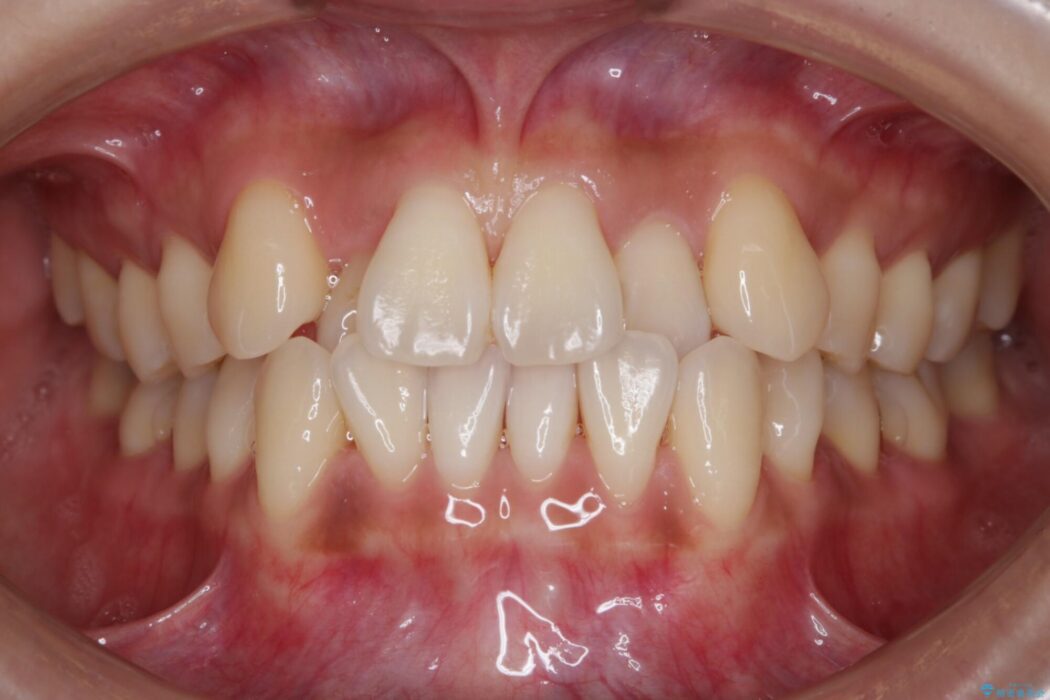

前歯のガタガタを気にされて来院されました。

- 矯正治療後の保定が不十分だと後戻り(元の位置に戻ろうとする動き)をします